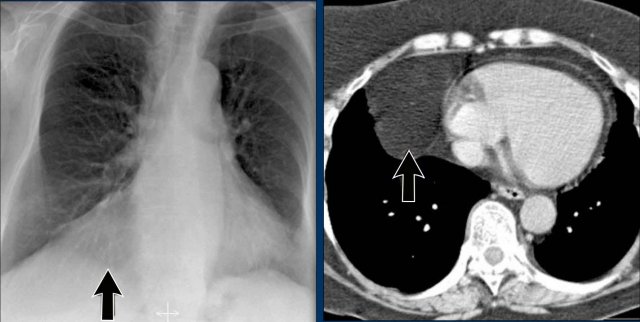

Displacement of the Azygoesophageal Line (2) – Subcarinal Lymphadenopathy

A common cause of displacement of the azygoesophageal line is subcarinal lymphadenopathy (station 7).

On the chest X-ray, note superior displacement of the azygoesophageal line just below the carina, consistent with enlarged subcarinal lymph nodes (black arrow).

Additional right paratracheal lymphadenopathy is seen, displacing the right paratracheal stripe (white arrow) and deviating the trachea to the left.

Continue with PET-CT...

PET Imaging

• PET-CT demonstrates extensive hypermetabolic lymphadenopathy in the mediastinum and neck, which is more conspicuous than on chest radiography.

• Cervical lymph nodes are involved—an important finding as they are accessible for biopsy.

Continue with images of CT and ultrasound...

CT Imaging

• Contrast-enhanced CT shows bulky subcarinal lymphadenopathy displacing the azygoesophageal recess and compressing the left atrium.

• Biopsy of a cervical node confirmed small cell lung carcinoma.